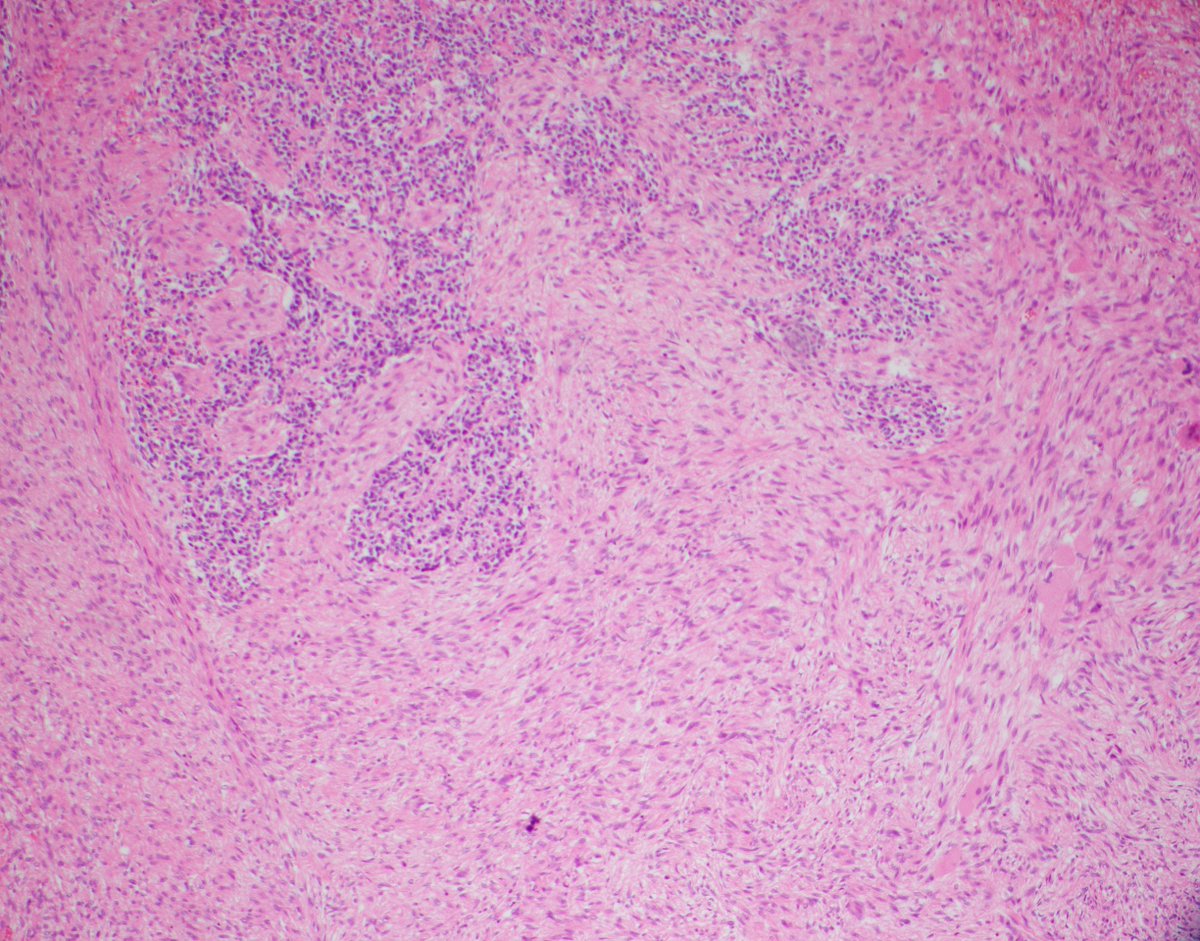

The first 2 were seminomas while the third was a diffuse large B cell lymphoma (DLBCL) exclusively involving the testis

#lymphoma#hemepathpic.twitter.com/NTcfZ5mFNh